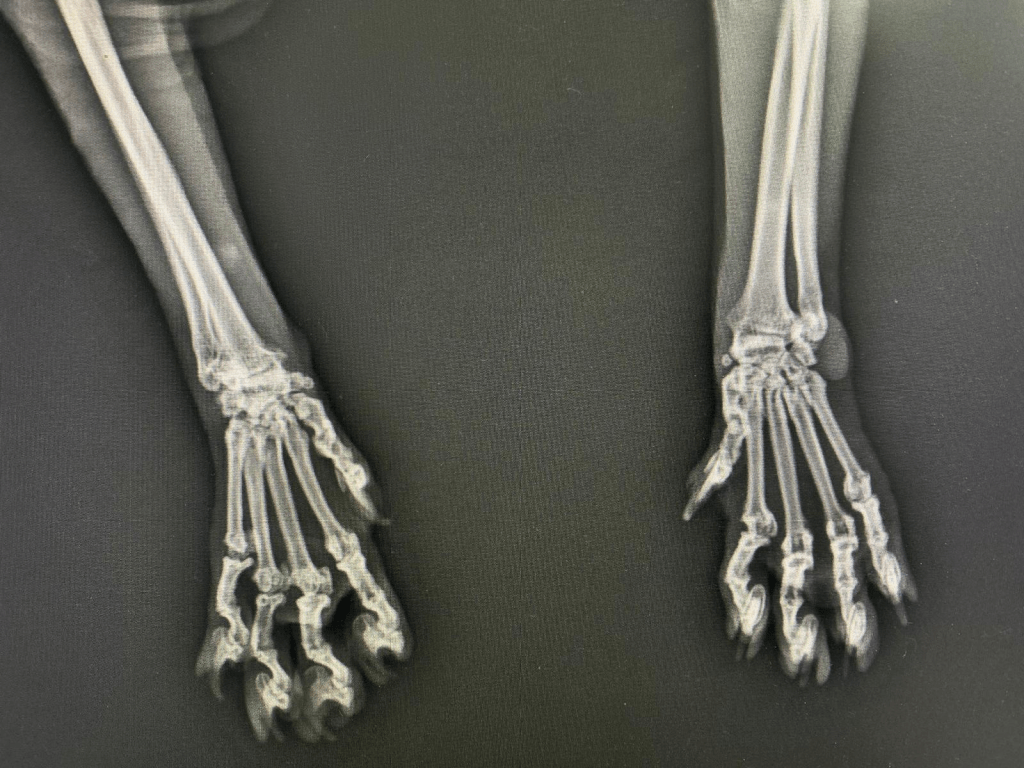

Osteokondrodisplazi hastalığına sahip Scottish Fold ırkı kedilerin anamnezinde genellikle; hareket etmede ve zıplamada isteksizlik, (kıkırdaktaki disfonksiyon sebebiyle) yürüyüşte bozukluk, topallık ve genellikle (bir ağrı göstergesi olan) kambur vücut duruşu ön plana çıkan davranışsal semptomlardır. Bunların yanında kuyruk omurlarının kaynaşmasından dolayı esnekliğini yitiren kuyruk; sert, kısa ve kalındır. Bacak kemiklerindeki hücre çoğalması ve yeni kemik oluşumu sebebiyle deforme olmuş, kısa ve kalın bacaklar görülür. Aynı şekilde

deformasyona uğrayan ayak parmakları da şekilsiz bir pati görünümüne sebebiyet verir. Radyografik incelemede ise; distal ekstremitelerde ilerleyici yeni kemik oluşumu ve topuk kemiğinin plantar yüzeyinde kemik tümörü (ekzostoz) oluşumu gözlenir. Bu ekzostozlar eklem ankilozuna (eklem oynaklığının azalmasına) yol açabilir. Yaygın osteopeni (kemiklerin zayıflaması) de lezyonlara eşlik eder. Bazı kedilerdeki klinik tablo çok şiddetli ağrılara sebep olurken kimisinde daha hafif şiddetli klinik tablolar gözlenebilir.